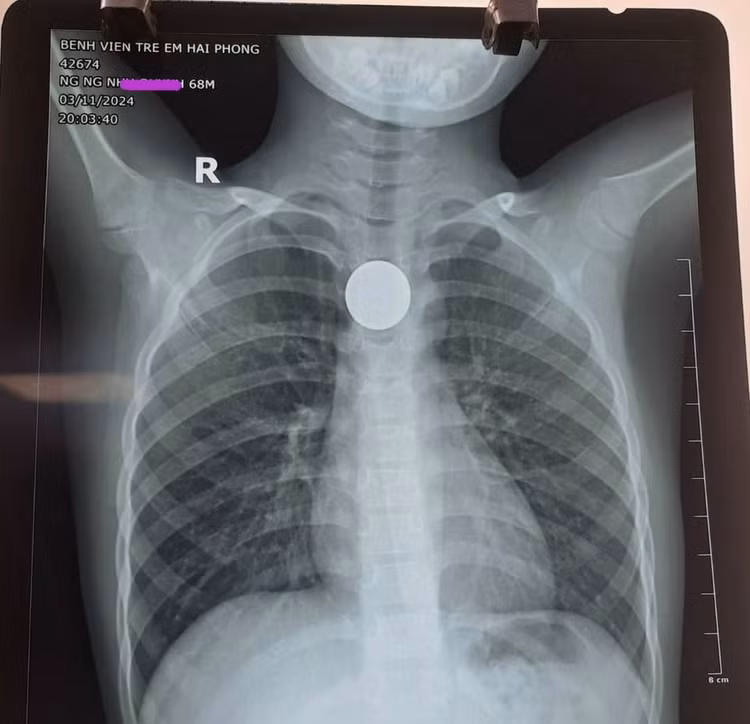

Cháu bé 6 tuổi ngụ tại Thủy Nguyên vừa được đưa tới Bệnh viện Trẻ em Hải Phòng tối ngày 11/03/2024 vì nghi nuốt đồng xu chơi game.

Theo lời kể của gia đình, trong khi đang chơi với bạn, cháu Nguyễn Ngọc N.Q có nuốt đồng xu chơi game, sau nuốt cháu khó chịu, đau vùng cổ, buồn nôn, gia đình đã kích thích cho cháu nôn ra, càng cố nôn cháu càng đau, tức ngực nhẹ.

Kết quả trên hình phim, các bác sĩ phát hiện một vật cản âm tròn đều như mô tả đồng xu, mật độ như kim loại nằm tại vị trí thực quản ngực

| Đồng xu chơi game trong thực quản bệnh nhi |

Cháu bé nhanh chóng được tiến hành gây mê, nội soi và gắp kịp thời đồng xu kích thước gần 3cm ra khỏi đoạn 1/3 giữa thực quản an toàn. Sau khi được nội soi gắp thành công đồng xu ra khỏi thực quản, hiện sức khỏe cháu bé đã ổn định.